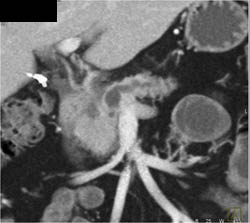

Diagnosis

Intraductal Papillary Mucinous Neoplasm (IPMN)